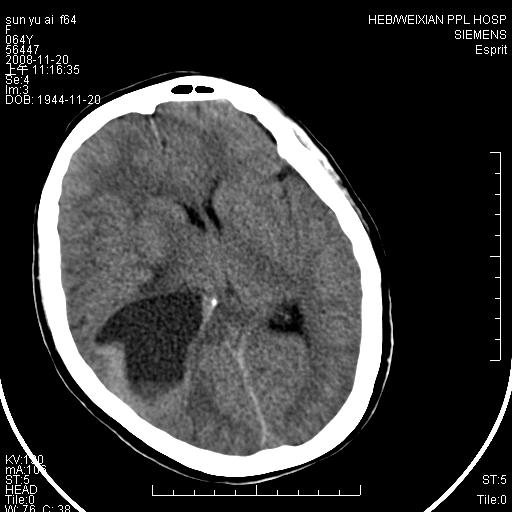

里面还有液平的,多考虑表皮样囊肿,其次考虑胶母及脑膜瘤等,

影像表现:侧脑室三角区附近可见以形态不规则的囊实性肿块,其中以囊性成分为主,实性成分为辅,边缘清晰,未见水肿,轻度占位效应,脉络丛钙化向内上移位,右侧脑室轻度扩大(也许体位所致),

影像诊断:1室管膜瘤

2胆脂瘤 建议增强吧

1、右侧大脑半球囊实性占位病变,以囊性变为主,实性部分位于病变外后侧,周围无明显水肿,占位征象明显。

2、多考虑胶质瘤可能性大。

有液平的,多考虑表皮样囊肿,胶质瘤可能?

右颞顶叶囊实性占位,有壁结节。考虑间变性胶质瘤可能性大,建议增强进一步检查。

右颞顶叶囊实性占位,有壁结节,考虑胶质瘤可能性大,建议增强进一步检查。